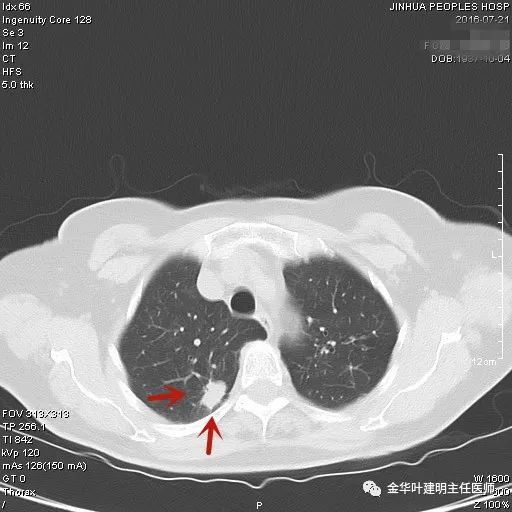

上图示浸润性腺癌典型表现。实性结节,有细毛刺征,有血管进入病灶,部分地方有浅分叶。